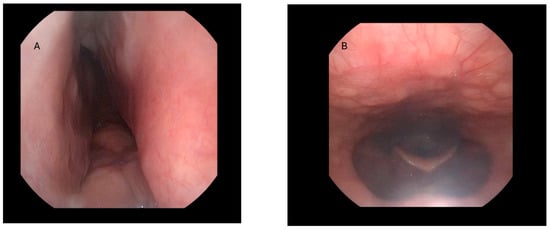

- Preoperative drug-induced sleep endoscopy (DISE) demonstrating potential benefit from MA, confirmed through mandibular advancement maneuvers.

4.4. Impact on Airspace